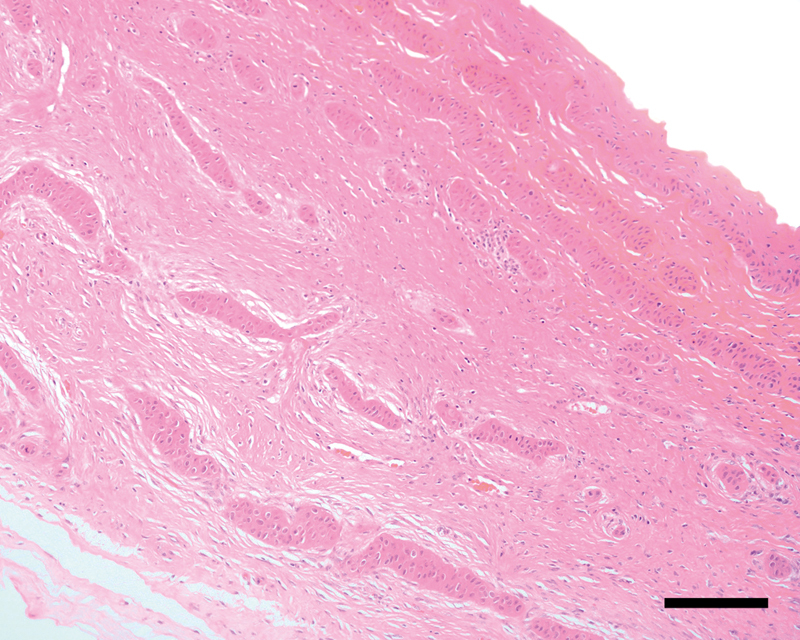

A 17-year-old Appaloosa mare was referred for evaluation of presumed refractory keratitis of the left eye. Gross examination revealed ocular discomfort and corneal neovascularization with a nasal focal opacification affecting approximately 40% of the corneal surface. On ophthalmic examination, extensive subepithelial to mid-stromal vascular branching accompanied by a homogeneous white, dense opacification, which affected up to 80% of the total corneal thickness, were apparent. Signs of concurrent uveitis were absent. Deep-stromal lamellar keratectomy with a conjunctival pedicle graft was performed under general anesthesia. Histopathology confirmed a poorly differentiated corneal stromal invasive squamous cell carcinoma (SI-SCC) with neoplastic cell extension to the surgical margins. Postoperatively, 4 topical mitomycin C 0.04% chemotherapy cycles combined with oral firocoxib therapy were initiated. Seven months after surgery, regrowth of the SI-SCC was clinically suspected. A total volume of 1 ml bevacizumab 2.5% was administered in the standing sedated horse via 3 mid-stromal corneal injections. Four weeks later, intrastromal bevacizumab injections (ISBIs) were repeated, however, this time the solution was injected directly into the main corneal vessel branches.Seven weeks after the second ISBIs, the left eye was comfortable and significant remission of corneal vascularization and opacity was recognized. No recurrence has been noted for a follow-up period of more than 53 months.Equine SI-SCC usually has a very poor prognosis for globe maintenance. To the authors' knowledge this is the first report of well-tolerated intrastromal antivascular endothelial growth factor adjunctive therapy with bevazicumab 2.5% and SI-SCC resolution after a multimodal treatment approach.

Abstract Image